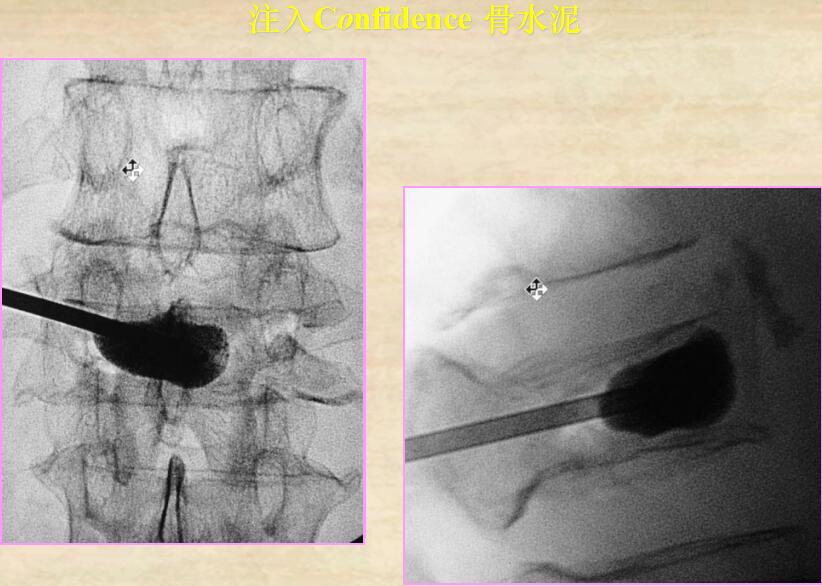

1、插入穿刺針

2、調(diào)和骨水泥裝入容器

3、專用的骨水泥調(diào)和裝入工具,操作簡便快捷

4、單側(cè)穿刺入路